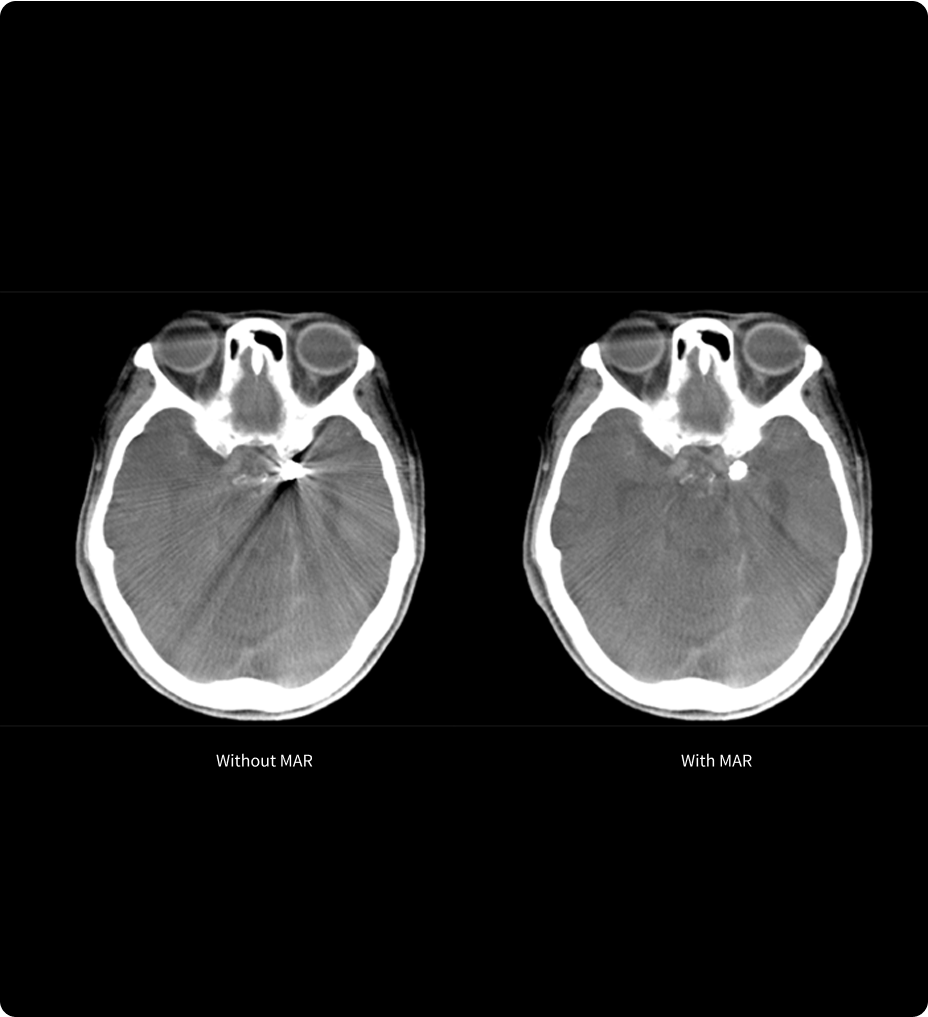

MAR11

Réduisez les artefacts métalliques, optimisez la qualité d’image.

MAR11 (Metallic Artifact Reduction) est une technologie de pointe permettant de réduire les artefacts causés par les objets métalliques présents dans le corps, tels que les implants. Ces artefacts peuvent en effet masquer des détails anatomiques importants, ce qui rend difficile pour les cliniciens de poser des diagnostics et planifier les traitements avec précision.

Améliorant la qualité d’image, MAR11 est un outil précieux pour renforcer la précision et la sécurité des procédures peu invasives.